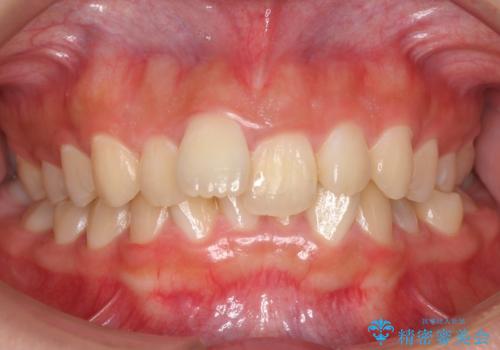

前歯が大きいのが気になる セラミックで整えたい

- 前歯が大きいのを揃えたいとのことでした。

少し削って長さを短くして様子を見ましたが、どうしても気になるとのことでした。

隣の前歯が小さいため、4本被せてバランスをとりました。

4本セラミックにすると大きさだけでなく、色も揃えられるのでおすすめです。

- ジルコニアクラウン(スタンダード) 11万円×4本、仮歯 1万円×4本費用は治療当時の料金となります

歯の向きは悪くなかったため、神経は取らずに治療しました。